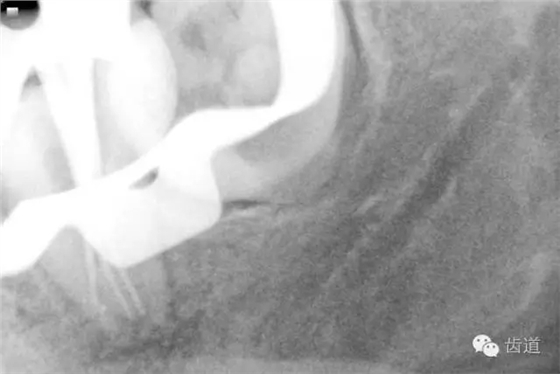

17. X線主尖片

4. 術(shù)后根充X線片